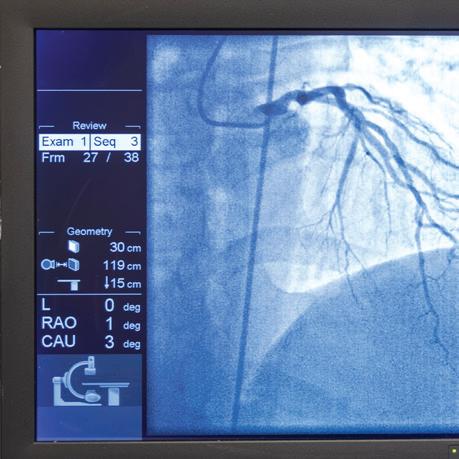

We are a designated Level III Trauma Center, Level III Neonatal Facility, and Maternal Level III Subspecialty Care Center, reflecting our advanced capabilities in managing high-risk emergencies and complex births. These designations reinforce the confidence families place in us during life’s most critical moments.

Our clinical distinctions include The Joint Commission’s Gold Seal of Approval® as an Advanced Primary Stroke Center and a Chest Pain Center, underscoring our rapid coordinated response in time-sensitive conditions. Moreover we received the HCAHPS Pinnacle of Excellent award for patient satisfaction and Lantern Award by the Emergency Nurses Association (ENA). This prestigious recognition honors emergency departments that exemplify exceptional and innovative performance in leadership, practice, education, advocacy, and research.

• Adding a 10th operating room dedicated to neurosurgery

• Upgrading radiology services with SPECT/CT imaging

• Introducing Breast MRI for advanced cancer detection, high-risk screenings, and implant integrity evaluations